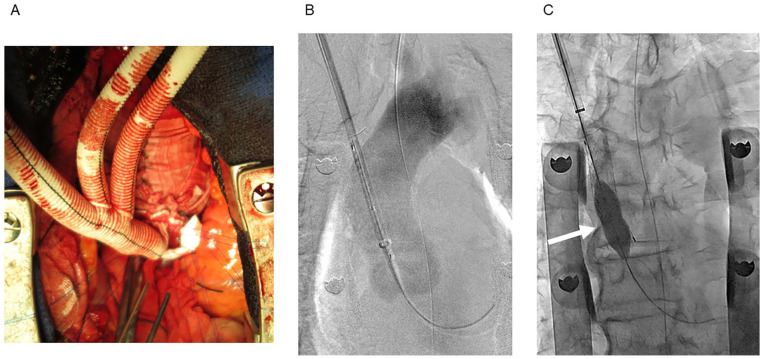

Background: Hybrid aortic arch repair with debranching of the supra-aortic vessels carries a high risk of cerebral infarction and fatal complications associated with side clamping of the ascending aorta. A previous study had reported the "real chimney" technique, a novel method for clamp-free total debranching thoracic endovascular aortic repair with the ascending aortic sleeve banding with dacron. In this study, we aim to build upon this foundation by presenting our experience with the early and midterm outcomes of this technique.

Methods: We retrospectively reviewed the medical records of 61 consecutive older adult patients with aortic arch pathologies and a high risk of open repair who underwent total debranching thoracic endovascular aortic repair using the real chimney technique at our institution between January 2014 and June 2022. This technique was used to anastomose the ascending aorta with the main trunk of the triple-branched prosthetic graft.